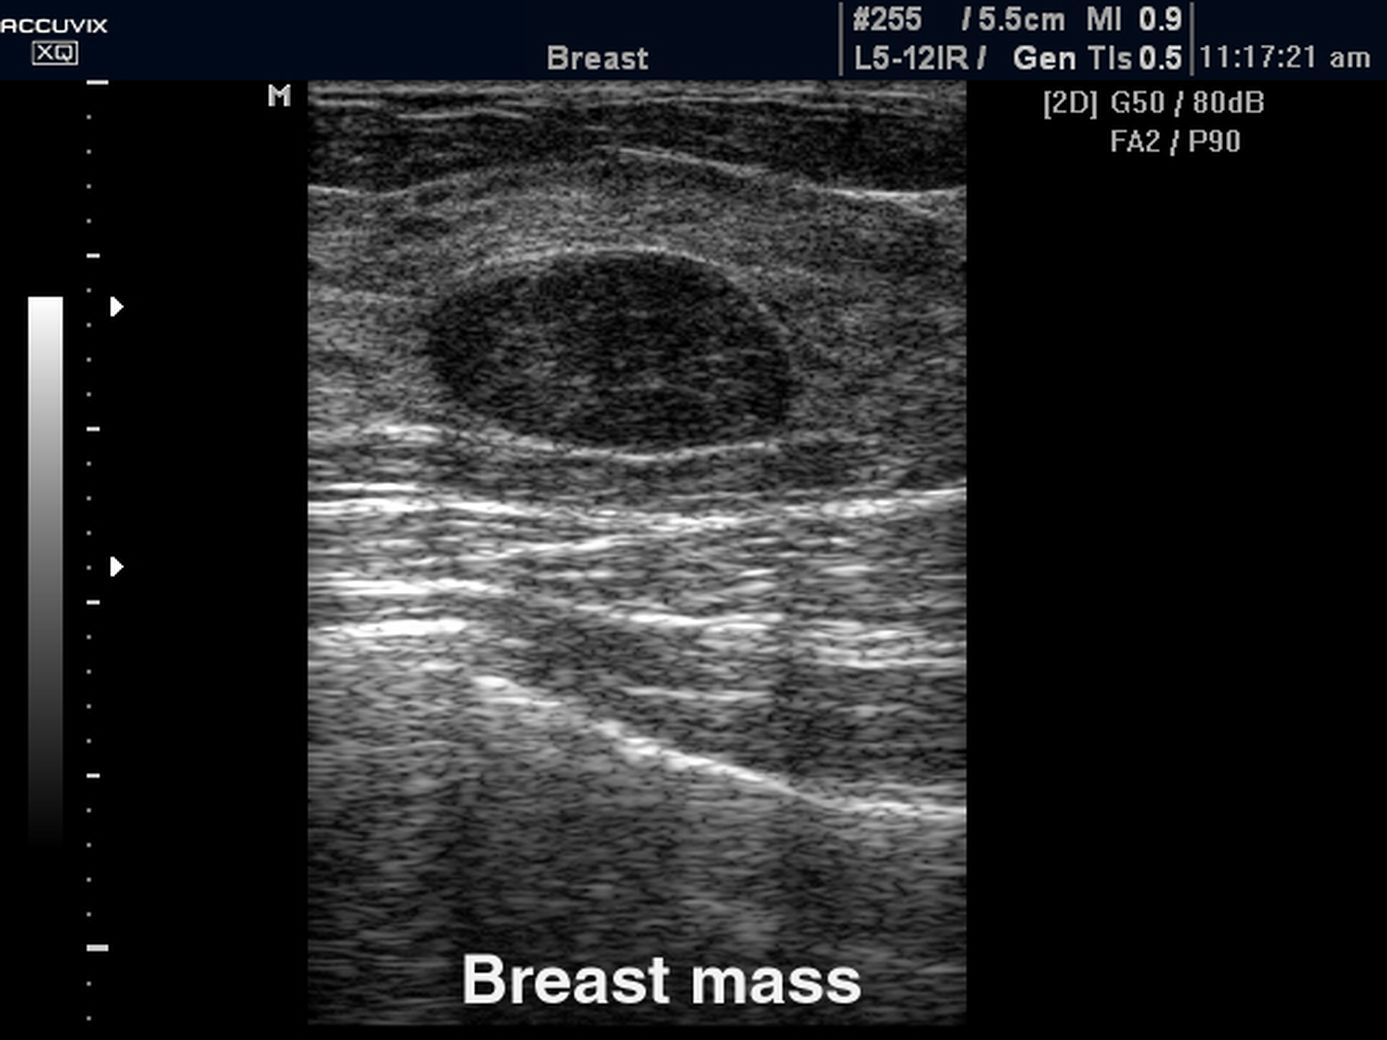

Фиброзно-кистозная мастопатия на УЗИ